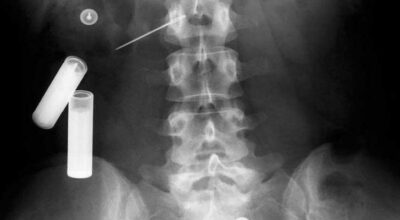

Esta recopilación de imágenes recoge alguna de las situaciones más estrambóticas que se han podido dar en una sala de rayos X. Todas ellas tienen algo en común: Son objetos extraños para el cuerpo humano que, de alguna manera han encontrado una vía de entrada, pero se han perdido a la hora de encontrar la de salida.

Muñecas de juguete descabezadas, botellas, armas, frascos, botes de plástico, teléfonos y hasta una cinta de casete pueden encontrarse en esa suerte de “punto limpio” al que ha quedado reducido el interior de los afectados.